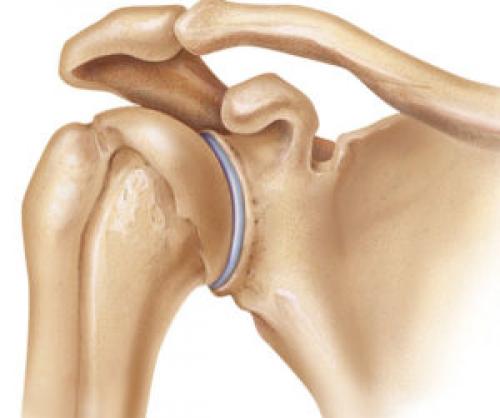

Лопатка – это плоская широкая кость, которая расположена свободно в толще мышц по задней поверхности грудной клетки. Между лопаткой и грудной клеткой находятся синовиальные сумки для уменьшения трения при движениях. Если при движениях возникают щелкающие звуки, хруст и прочие звуковые феномены, врачи говорят о синдроме «щелкающей лопатки».

К костям плечевого пояса относятся плечевая кость, ключица и лопатка. Две большие мышцы берут начало на внутренней поверхности лопатки. Это подлопаточная и передняя лестничная мышцы. Подлопаточная мышца прикрепляется к плечевой кости вблизи плечевого сустава, а передняя лестничная к ребрам на боковой поверхности грудной клетки.

Синовиальная сумка представляет собой наполненный вязкой тягучей жидкостью (синовией) мешочек, расположенный между трущимися поверхностями. Синовиальные сумки расположены между подлопаточной и передней лестничной мышцами, а также между передней лестничной мышцей и грудной клеткой. Воспаление бурсы носит название бурсита. Это заболевание может проявляться болью, а также звуковыми феноменами (треск, щелкание и проч.).